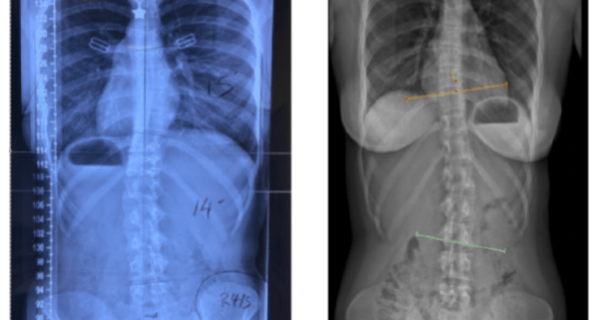

Degenerative scoliosis is caused by the gradual wear and tear of the spine’s facet joints and discs, which can result in an abnormal curvature. The condition is most commonly observed in individuals over 50, with women being disproportionately affected, especially after menopause.

- a visible curvature of the spine